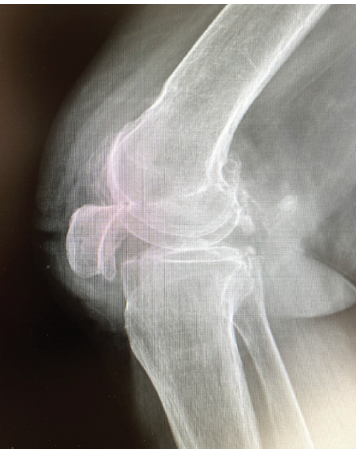

Locked Knee and Inferior Patellar Dislocation in an Elderly Patient: A Case Report and Review of the Literature